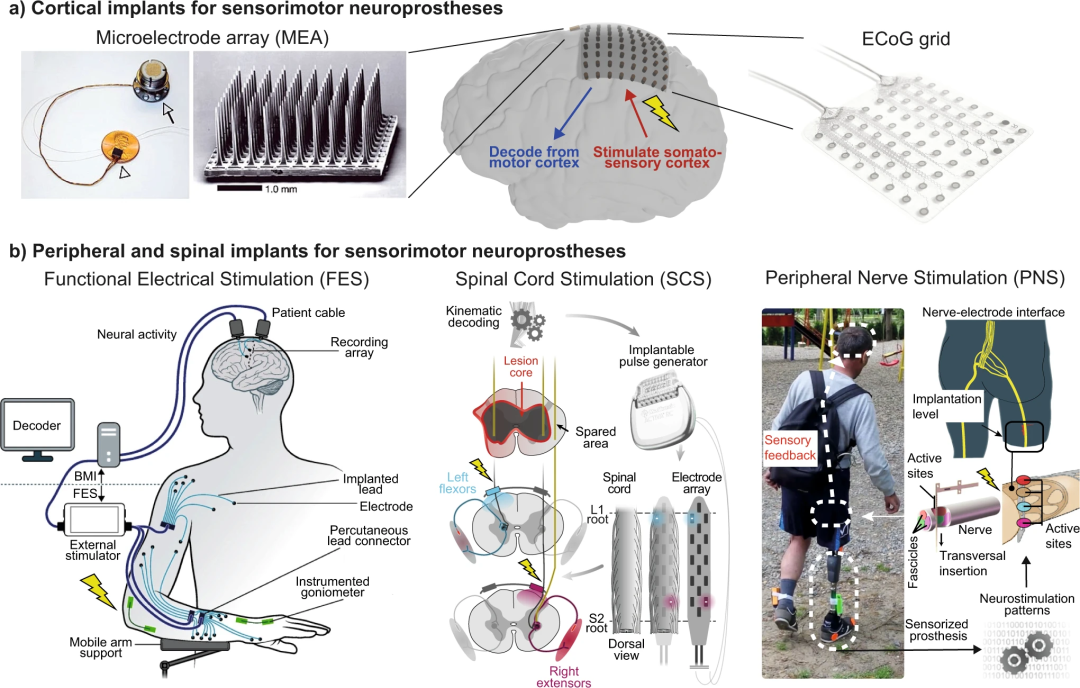

BMI不应被视为与神经刺激方法分离的一种神经义肢,而应被视为操作它们的控制信号的潜在来源。这些不同的研究为神经义肢与神经系统的双向接口以及利用记录和刺激能力铺平了道路(如图1所示)。

图1.感觉运动障碍的神经假体技术。a.通常用于感觉运动神经假体的皮质植入物可分为两类:皮质内MEA,如Utah阵列(10 × 10 Utah阵列),以及不同规格的硬膜外或硬膜下ECoG带或网格(图示为8 × 8 ECoG网格,接触直径4毫米,间距10毫米)。这些植入物既可以记录神经生理信号,也可以传递电刺激。b. 感觉运动神经假体的外周和脊柱植入物针对FES的运动神经或肌肉,硬膜外SCS的脊髓,或PNS中的感觉神经以获得体感反馈。这里展示的所有应用都使用了这些植入物来进行电刺激。闪电标志表示神经刺激。